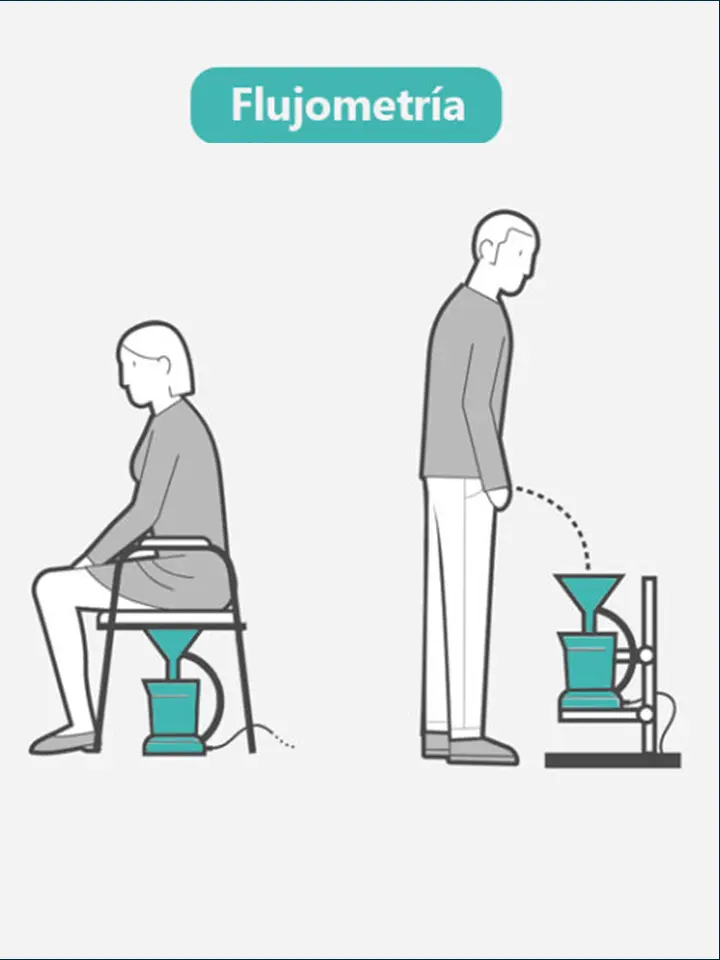

La uroflujometría es una prueba no invasiva que mide el volumen de orina eliminada, la velocidad a la cual se elimina y el tiempo que toma la eliminación. Esta prueba se utiliza para evaluar el funcionamiento de las vías urinarias y detectar posibles obstrucciones o problemas en la micción.

Rapido

No invasivo

Sin mayores complicaciones